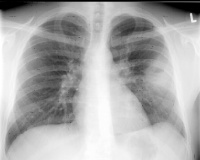

Als Besonderheit ist an das Q-Fieber zu denken, das sich überwiegend mit Pneumonien und Hepatitiden manifestiert. Die Übertragung des Erregers Coxiella burnetii geschieht vor allem durch Zecken insbesondere auf Schafe und Ziegen. Die Q-Fieber-Pneumonie wird auch in den Auslandsstandorten der Bundeswehr gesehen, das Synonym Balkan- Grippe spricht für sich. Die Übertragung erfolgt meist durch Inhalieren von mit getrocknetem Faeces kontaminiertem Staub, insofern war in der oben geschilderten Fallvignette des jungen Soldaten daran gedacht worden. Dies hat sich bei ihm jedoch nicht bestätigt, ein Infiltrat konnte im Verlauf sicher ausgeschlossen werden. Sicherlich wird wie in dem geschilderten Fall bei dieser Symptomkonstellation häufig eine virale Erkrankung oder gewöhnliche Pneumonie vorliegen, eine serologische Untersuchung sollte aber bei der oben genannten Konstellation zweimal (im Abstand von 10-14 Tagen) durchgeführt werden. Das Röntgenbild bei Q-Fieber-Pneumonie entspricht oft einer atypischen Pneumonie mit eher gering ausgeprägtem Infiltrat (s. Abb. 3), zusätzlich besteht oft eine Hepatitis und eine pleurale Reizung mit Husten und atemabhängigen Throaxschmerzen.

Somit ist im Verlauf der Krankheit die Spannbreite der klinischen Darstellungen groß. Bei therapieresistenten Infiltraten, insbesondere der Lungenoberlappen, ist an die Tuberkulose zu denken. Die Abb. 4 zeigt eine Tuberkulose bei guter immunologischer Abwehrlage des Patienten und ließe beispielsweise auch an eine Raumforderung denken. Daneben sind alle Bilder von „normalen“ Pneumonien denkbar. Der chronische Verlauf mit Ausbildung von Veränderungen, die sich durch den andauernden Entzündungsprozess entwickeln wie Lungengerüstumbau, narbige Verziehungen und Entstehen von Kavernen lassen oft mehr oder weniger sicher eine Tuberkulose bereits radiologisch erkennen. Der Patient aus der Fallvignette zeigte CT-radiologisch das in Abb. 5 gezeigte Bild einer Miliartuberkulose, das schon fast an eine Lungengerüstkrankheit erinnert. Zusätzlich bestand bei diesem Patienten das Bild einer Abdominaltuberkulose mit Aszites.